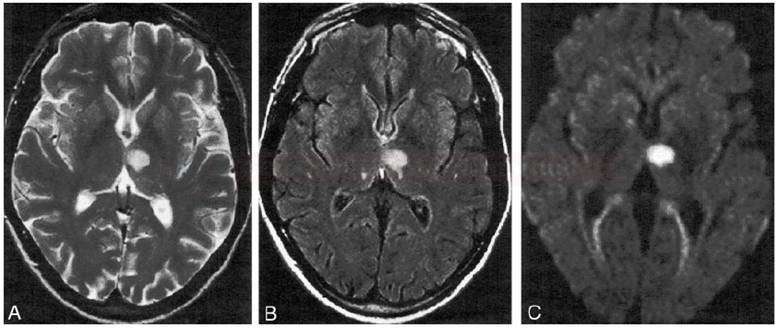

One of the most prominent trends in the TIA market is the growing emphasis on early diagnosis. TIAs are often overlooked, as their symptoms may be temporary and resolve before patients seek medical attention. However, advancements in diagnostic imaging, such as magnetic resonance angiography (MRA) and computed tomography (CT) scans, have enabled more accurate and timely detection of Transient Ischemic Attack Market. The introduction of mobile and portable diagnostic devices is also playing a role in improving early detection in both clinical and emergency settings.